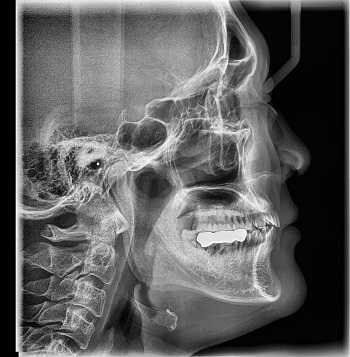

2. Рентгенография:

• Серповидная оссификация около задненижнего края суставной впадины

• Лучше видно на аксиллярной проекции или угловой передне-задней проекции (проекция Беннетта: краниальный наклон 5°)

(Слева) На аксиллярной рентгенограмме видна оссификация по заднему краю суставной впадины у бейсбольного питчера.